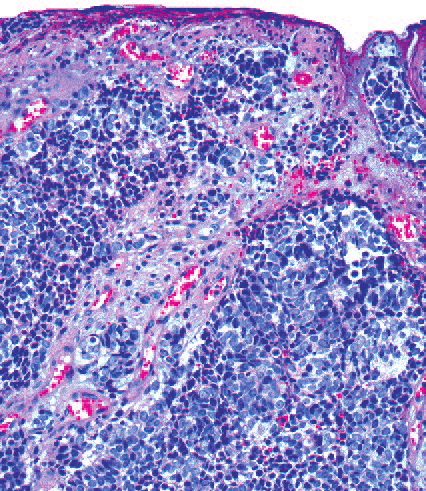

merkel-cell-carcinoma